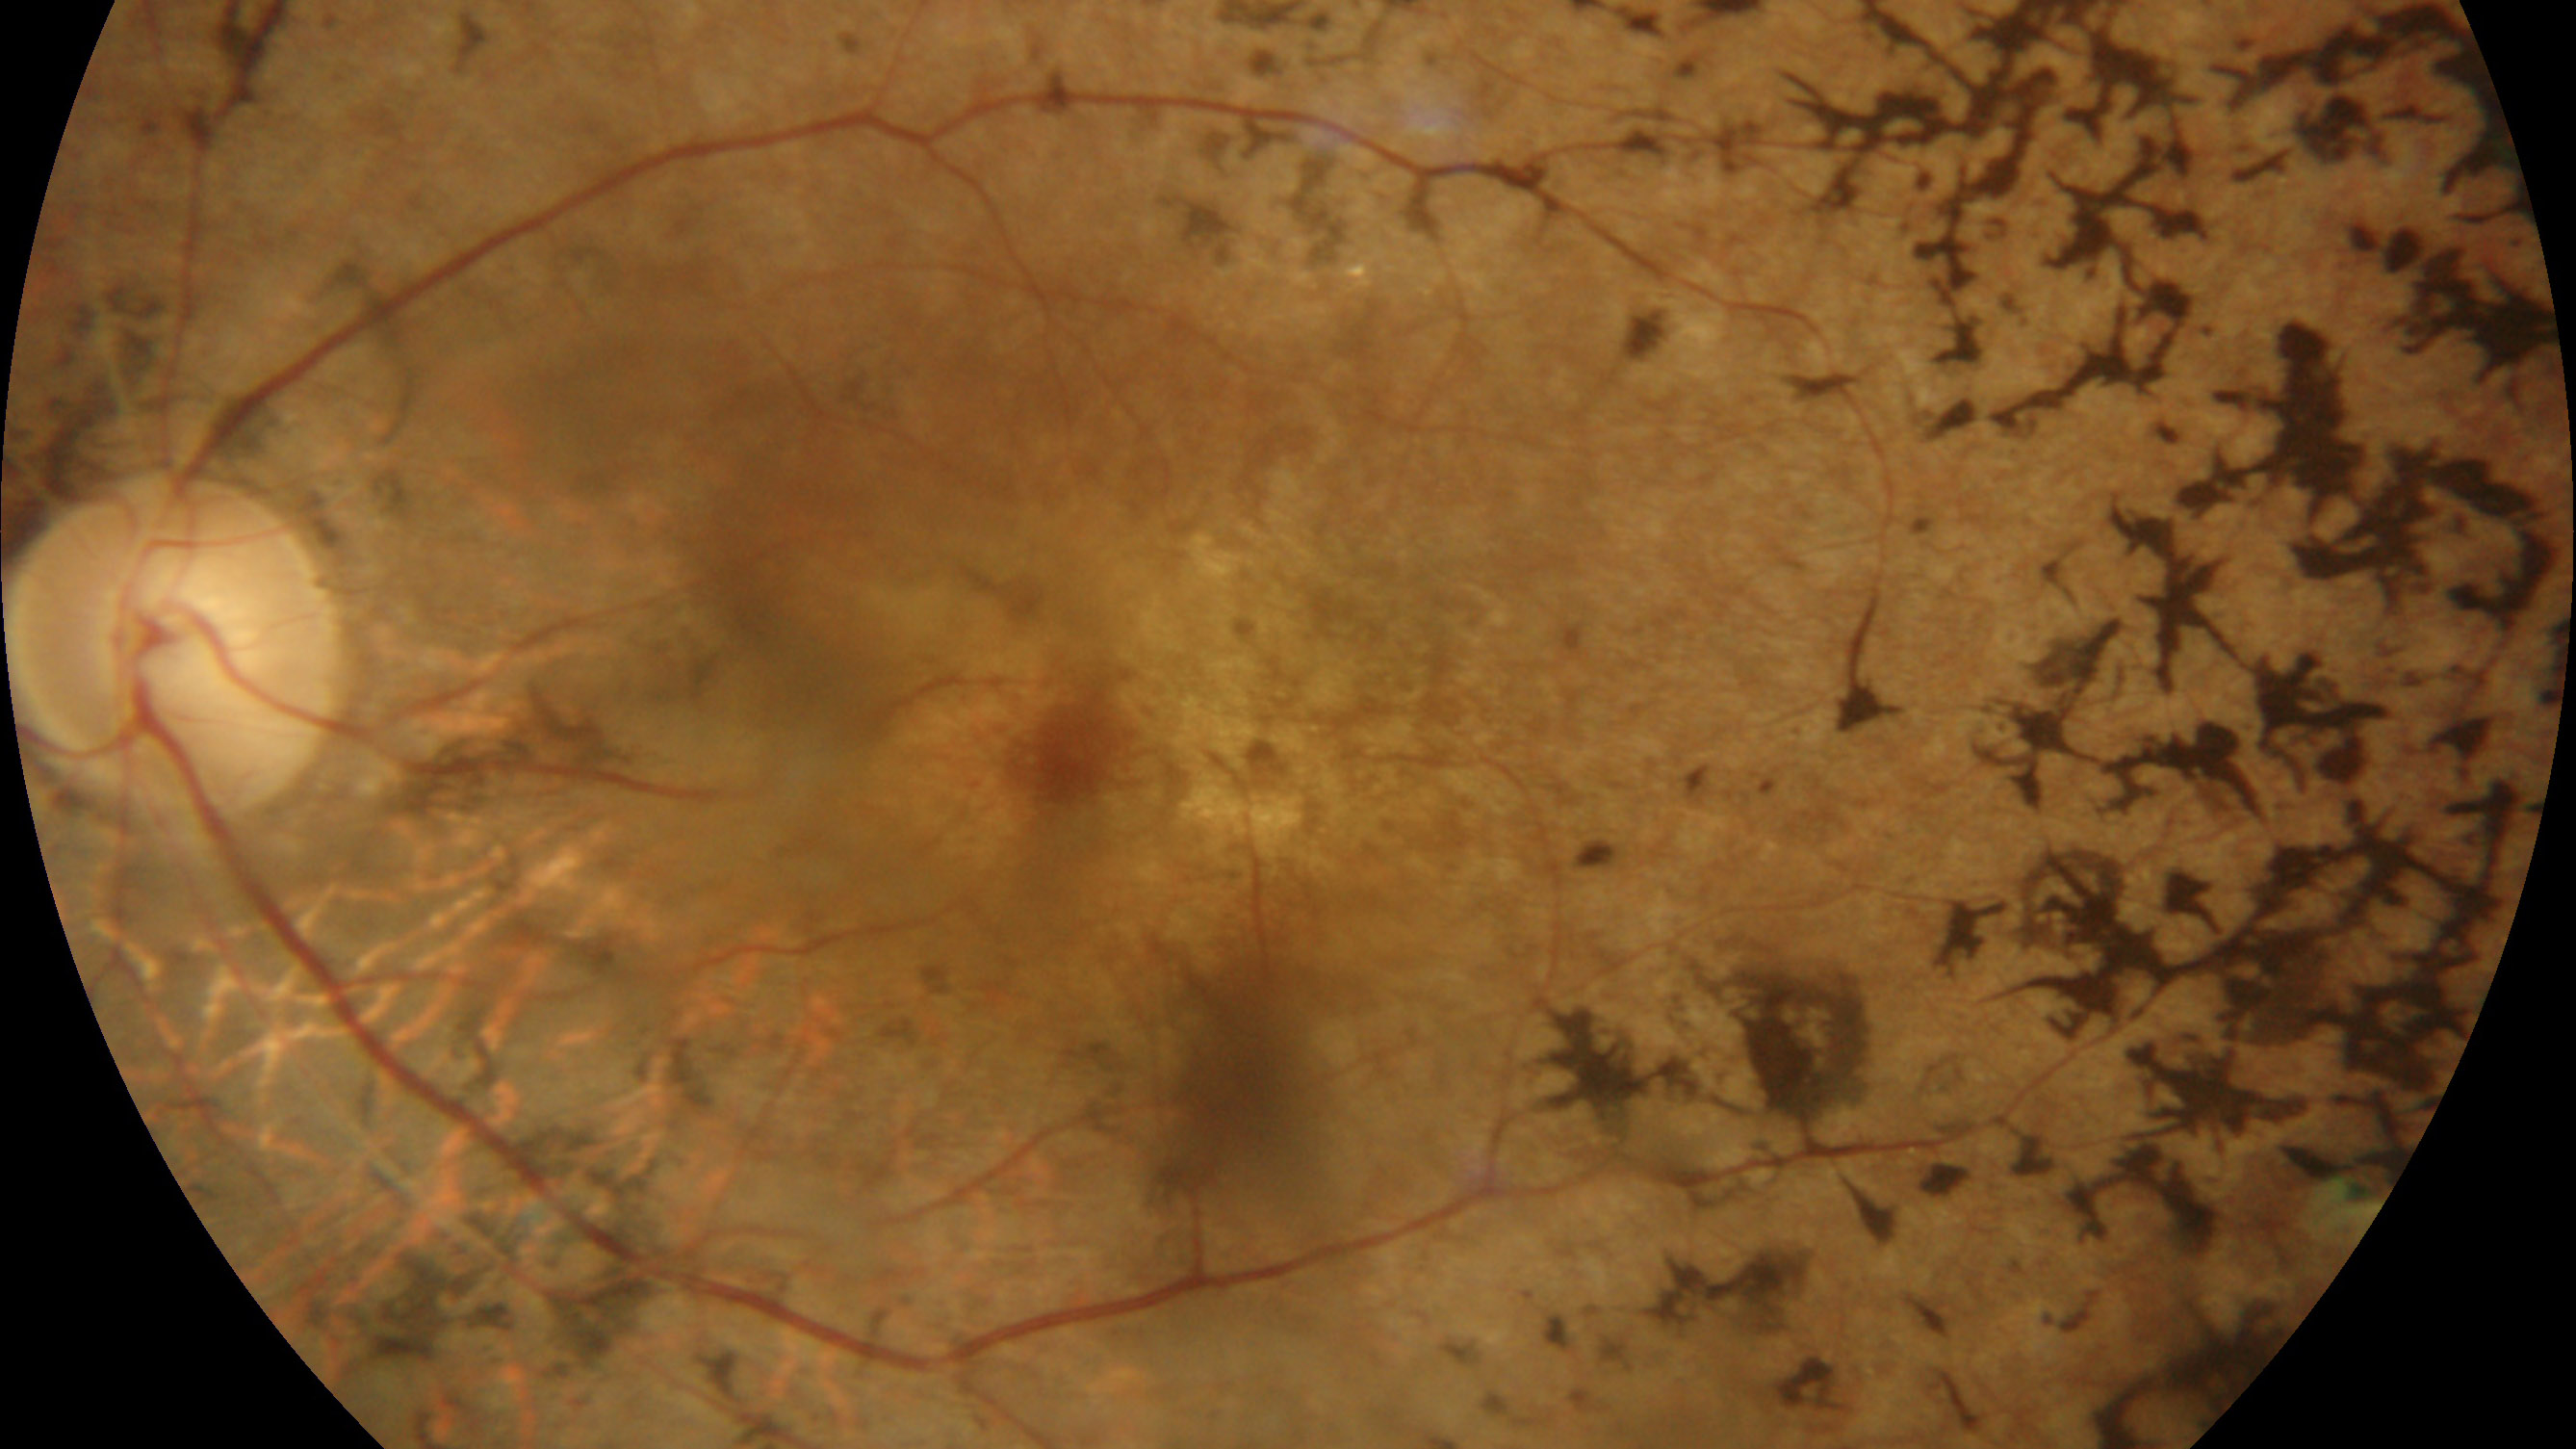

2. 図 01 図 02

3. 眼底所見は粗造()色調異常,網膜血管の狭細化,骨小体様と言われる色素沈着,視神経乳頭の黄色萎縮が特徴である.網膜色調の変化は視細胞(外節)の再生能と色素上皮細胞の貪食能の異常のためで,般に後極部より外側の赤道部にかけての中間帯に顕著である.初期変化が血管アーケード付近に始まるようにみえるのは,杆体細胞の密度が高い部分であるからといわれる.検眼鏡的に色素斑がわずかな病態が,無色素性 retinitis pigmentosa sine pigmentoである.

乳頭ドルーゼンを生じることが多い.視神経萎縮は,神経節細胞の変性に始まり上行性に進行する.これらのことが,蝋()様萎縮を呈する因となる.

硝子体中には色素の粒がみられる.遊離したメラニン色素顆粒,色素上皮細胞,ぶどう膜由来メラノサイト,およびマクロファージ様細胞で構成される微細な粒子で,硝子体全体に均一に分布する.